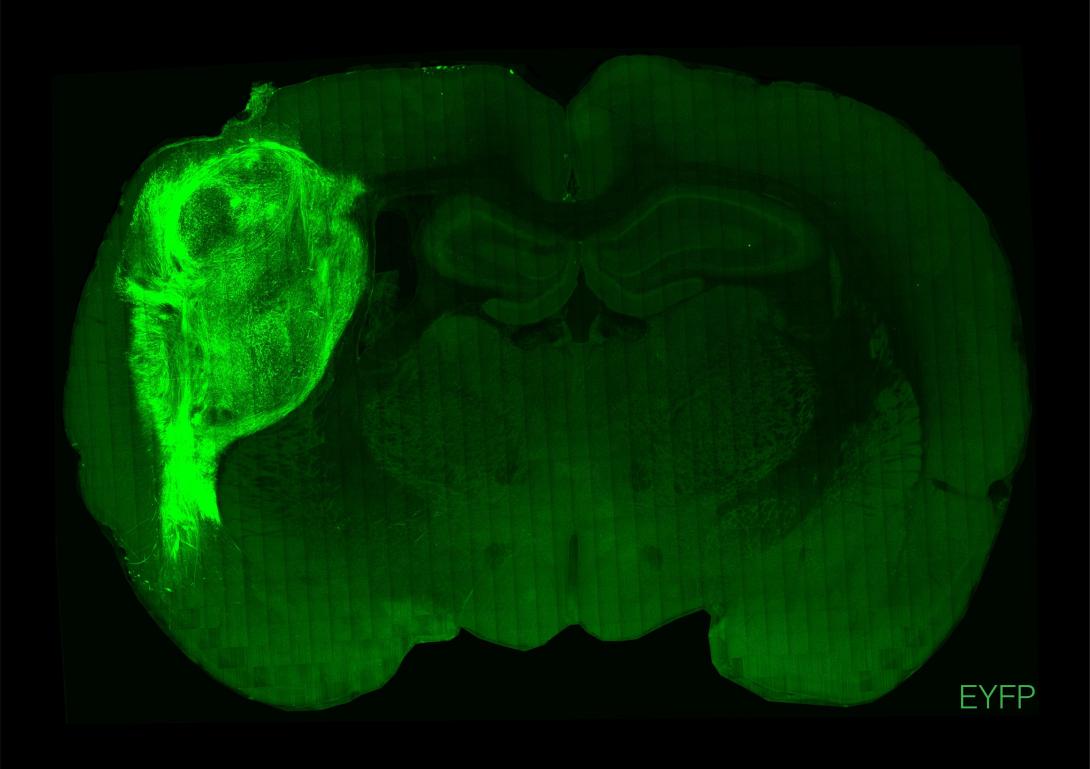

Οι ερευνητές, με επικεφαλής τον καθηγητή ψυχιατρικής και συμπεριφορικών επιστημών Σέρτζιου Πάσκα της Ιατρικής Σχολής του Πανεπιστημίου Στάνφορντ της Καλιφόρνιας, οι οποίοι έκαναν τη σχετική δημοσίευση στο περιοδικό "Nature", εμφύτευσαν οργανοειδή ανθρώπινου εγκεφάλου (κυτταρικές καλλιέργειες εργαστηρίου που δημιουργούν μίνι-εγκεφάλους) στον σωματοαισθητικό φλοιό του εγκεφάλου 100 νεογέννητων αρουραίων ηλικίας δύο έως τριών ημερών.

Οι εγκέφαλοι των ζώων ενσωμάτωσαν ομαλά το μόσχευμα, το υποστήριξαν με νέα αιμοφόρα αγγεία και το προστάτευσαν με ανοσοκύτταρα. Έτσι οι ανθρώπινοι νευρώνες πολλαπλασιάστηκαν και τελικά κάλυψαν περίπου το ένα τρίτο του ενός ημισφαιρίου του εγκεφάλου των ζώων. Όπως είπε ο Πάσκα, "ήταν σαν να προσθέτεις άλλο ένα τρανζίστορ σε ένα ηλεκτρονικό κύκλωμα". Τελικά οι ανθρώπινοι νευρώνες σχημάτισαν συνδέσεις (συνάψεις) με τα εγκεφαλικά κυκλώματα των αρουραίων και κατέληξαν να επηρεάζουν τη συμπεριφορά τους, ενώ δεν φάνηκαν κάποιες παρενέργειες στα ζώα.